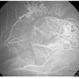

- pediatic retina, vascular anomaly

- Maria A. Martinez-Castellanos. Asociacion para Evitar la Ceguera en Mexico

- Imaging device

- RetCam II

- Fundus photograph of a 3-year-old boy with low vision, esotropia and leukocoria.